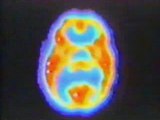

Chugani et al. usaron P.E.T. en 29 niños epilépticos cuyas edades variaban entre los cinco días y los quince años. El trabajo de 1987 es extremadamente importante porque fue la primera investigación de imágenes cerebrales que intentó bosquejar el desarrollo del cerebro desde la infancia hasta la adolescencia. Uno de los mayores descubrimientos fue que en todas las áreas cerebrales examinadas los niveles metabólicos alcanzaban valores de los adultos cuando los niños tenían aproximadamente dos años, y continuaban creciendo alcanzando valores dobles a los de niveles adultos para la edad de tres y cuatro años. Hacia los 9 años de edad la velocidad del metabolismo de la glucosa comenzaba a declinar y finalmente se estabilizaba en los valores adultos para fines de la adolescencia. Lo que los investigadores encontraron fue un período alto de actividad metabólica del cerebro que duraba desde los tres hasta los nueve años aproximadamente.